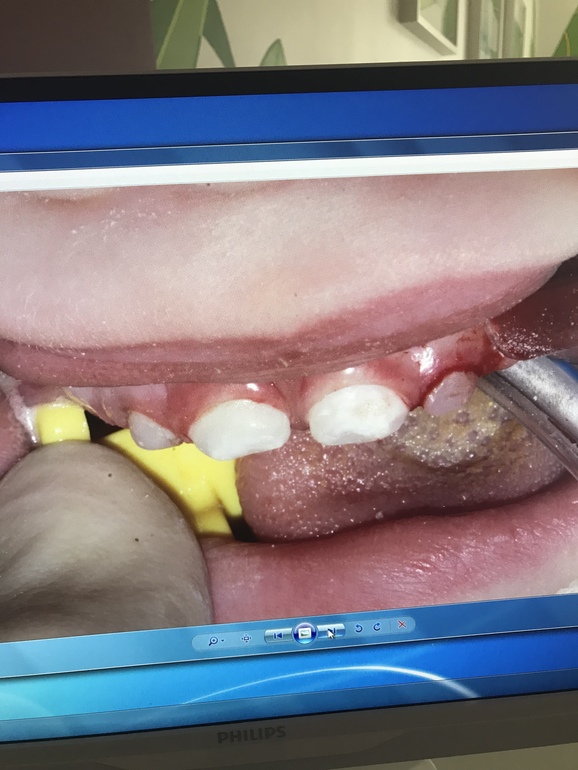

ЗубкиВчера вылечили и реставрировали зубы младшему. 4 зуба из 6... 2 часа под Севоран. Спасибо огромное врачам клиники Ваш Стоматолог они умнички и проделали колоссальную работу! У сына были 2 пульпита и кариес на передних верхних резцах. Обошлось лечение в 33.500₽ . Теперь ребёнок опять может без дискомфорта есть холодное/горячие / кислое / твёрдое ! наркоз перенесли хорошо , в пятницу едем на осмотр после операционный ! Для тех кому интересно приложу фото до и после

Зубки будем по необходимости реставрировать